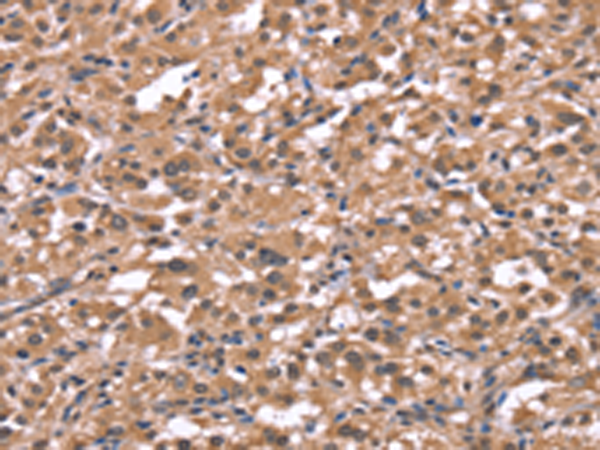

分类: 科研抗体货号: P04945别名: HH3R; GPCR97应用: WB,IHC反应种属: Human, Mouse